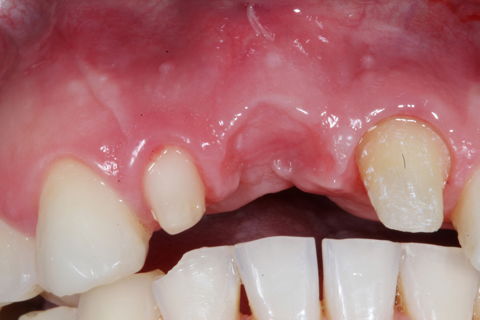

Caso inicial, evidenciando a perda de tecido na região do elemento 11.

Paciente com 30 anos do sexo masculino. Sua queixa era ausência do elemento 11. Como não queria passar por duas cirurgias pois não tinha tecido ósseo sufuciente para instalação de implante e elemento 21 já estava bem comprometido, com pouca estrutura de dente e tratado canal, demos a opção por uma ponte fixa em zircônia realizando enxerto de conjuntivo na região do pôntico para dar maior naturalidade ao caso.

No primeiro momento foi realizado instalação de provisório do 21 ao 12, para posterior cirurgia de enxerto de conjuntivo realizado pelo nosso periodontista Dr Felipe Breda .